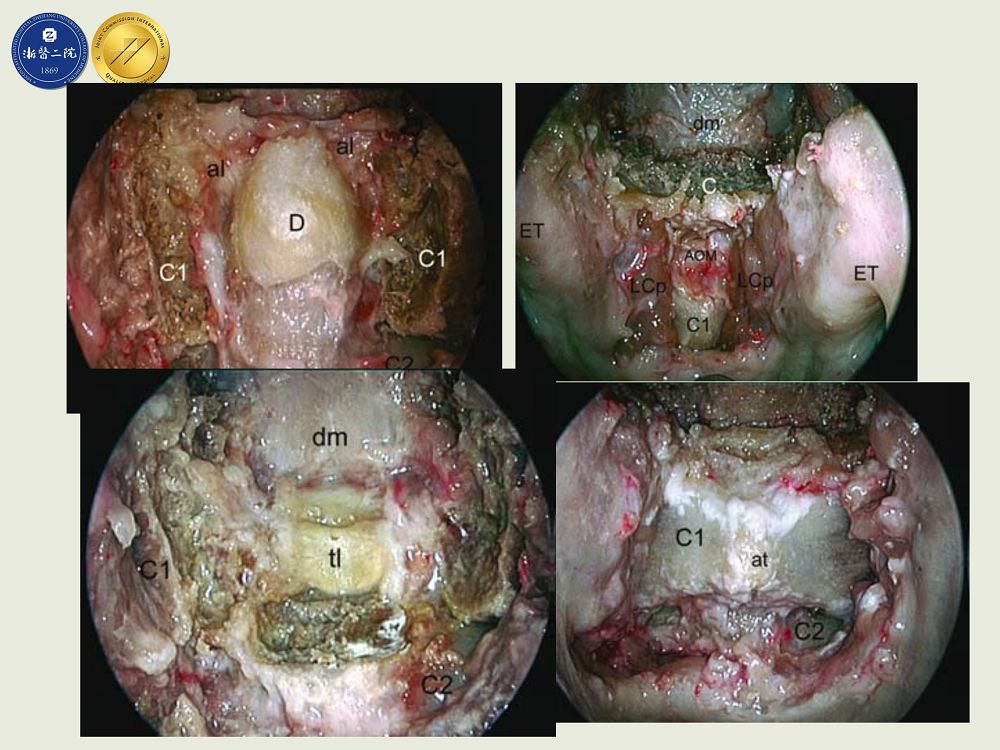

由来自包括北京天坛、上海华山等全国各大医院的十名选手经专家评委网上盲审最终进入总决赛。浙二神经外科在张建民主任安排下,由吴群主任带队,由洪远副主任医师在大会上展示一例高难度神经内镜下经鼻-斜坡-齿状突入路切除腹侧型枕骨大孔区脑膜瘤,凭借创新手术术式、娴熟手术技巧和满意手术疗效,获得大会评委一致认可,最终在总决赛中脱颖而出,获得唯一的特等奖。